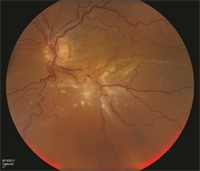

Complex retinal detachments due to PVR are associated with retinal scar tissue or membranes; these ultimately contract, pull, and stretch the retina, causing retinal tears or stretch holes. When the detached retina contracts, so-called “star folds” often develop (Figure 1).

Figure 1. A patient with complex retinal detachment due to PVR in the left eye. A retinal “star fold” is present in the inferior macular with associated subretinal fluid. (Photo courtesy Carl Regillo, MD)